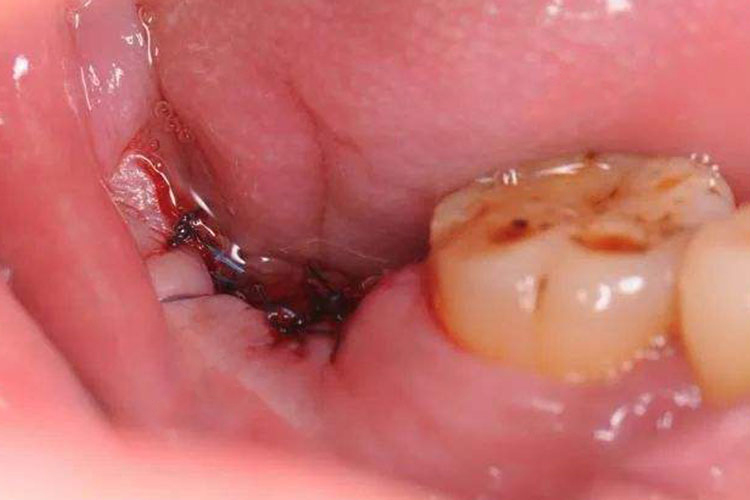

干槽症是拔牙创口急性感染的一种类型, 以下颌后牙多见, 特别是在下颌阻生第三磨牙拔除术后。在正常情况下,即使是翻瓣去骨拔牙术,正常牙洞创口的疼痛2~3天后会逐渐消失。如果拔牙2~3天后出现剧烈的疼痛,疼痛向下颌下区或头顶部放射,用一般的止痛药物不能缓解,则可能发生了干槽症。

临床检查可见牙槽窝内空虚,或有腐败变性的血凝块,呈灰白色。在牙槽窝壁覆盖的坏死物有恶臭,用探针可直接触及骨面并有锐痛。颌面部无明显肿胀,张口无明显受限,下颌下可有淋巴结肿大、压痛。组织病理表现为牙槽窝骨壁的浅层骨炎或轻微的局限型骨髓炎。